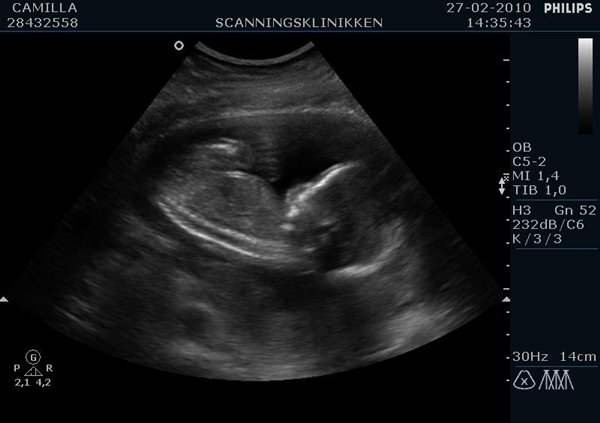

Ville lige ligge lidt billeder ind af min lille pige (Emilie?)  fra kønsscanningen igår

Vedhæftede fotos (klik for at se i fuld størrelse)

Billedet af hendes ædlere dele beviser 2stk skamlæber, (de to prikker)

Jordemoderen scannede mig fra alle leder og kanter og der var hverken tap eller pung at finde